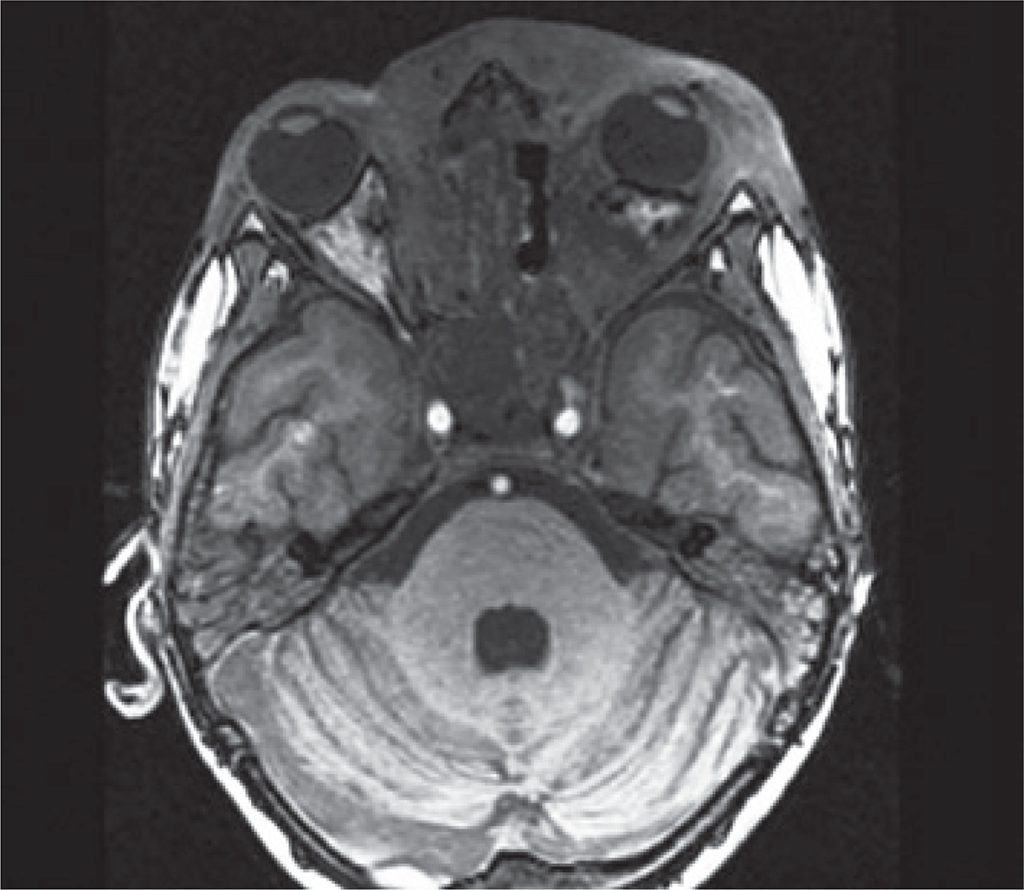

Figura 5

Diminuição da lesão infiltrativa que acomete o tecido subcutâneo, principalmente periorbitário esquerdo, e redução da proptose do mesmo lado. Redução da lesão na rinofaringe, hipofaringe e seios da face, em comparação com os anteriores